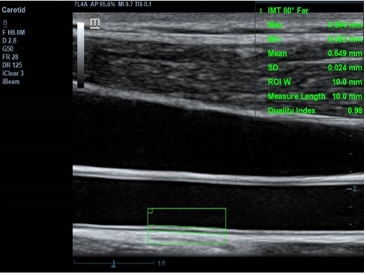

· 自动测量功能

内置丰富的自动测量功能,确保临床诊断的准确性和一致性,使操作便捷、快速。